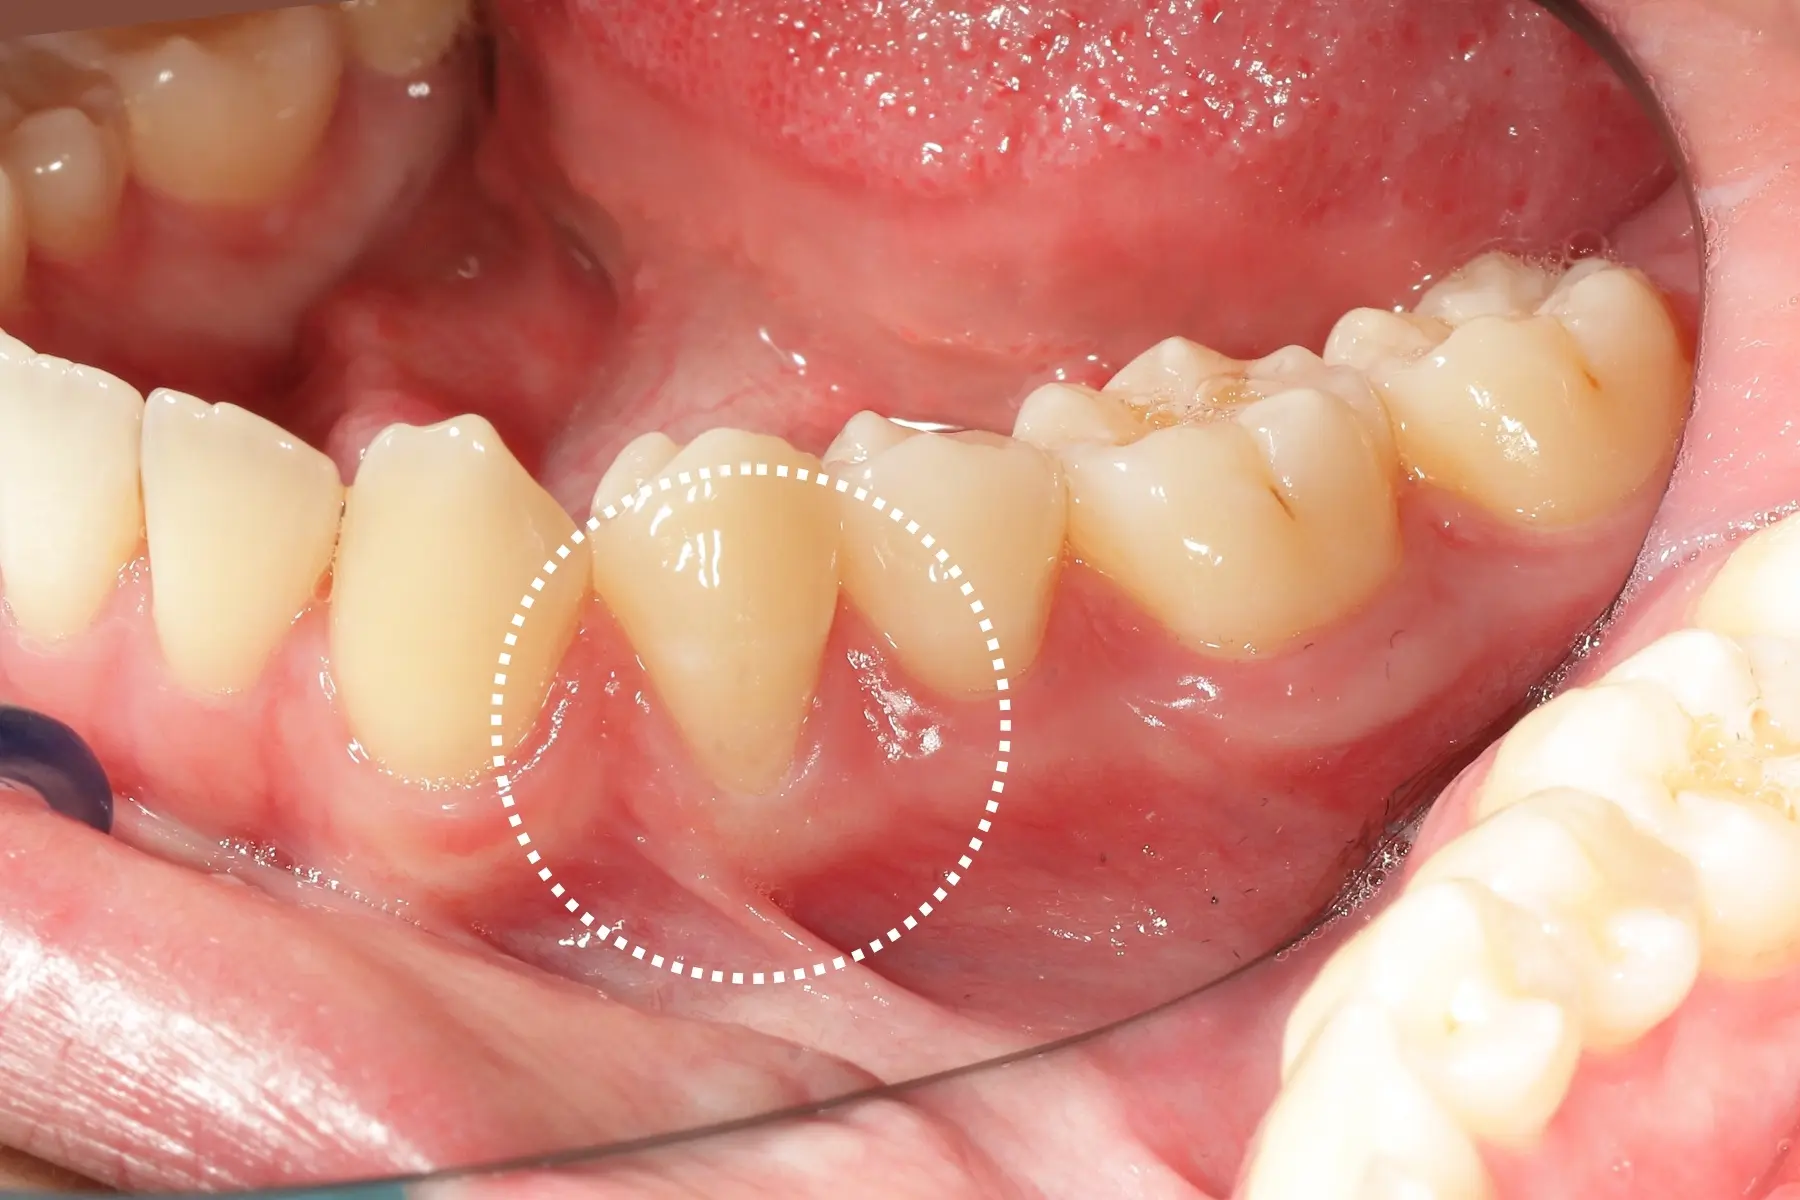

• 術前 42

術後 40

牙周治療

主治醫師

• 鍾國耀

治療時間

三次療程

主訴

右上前牙牙齦反覆腫脹化膿